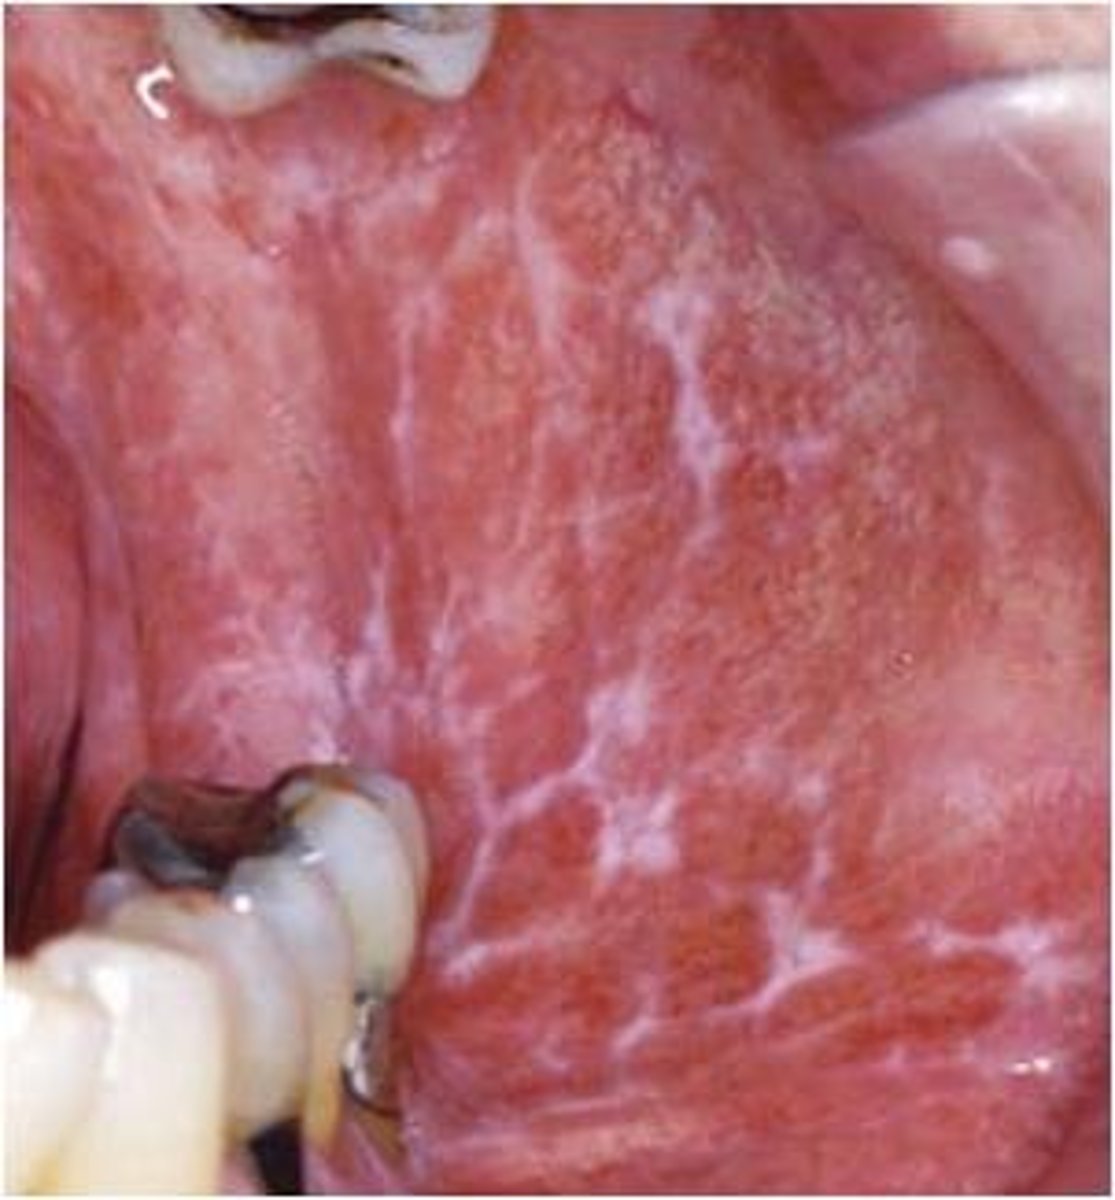

Reticular Lichen Planus

Hint: most frequent affects posterior buccal mucosa bilaterally

Hint: Lesions wax and wane